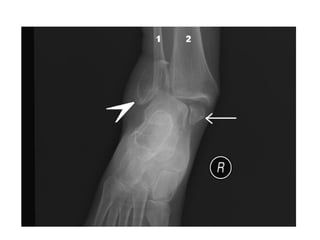

• Pott’s Fracture-Dislocation

• A Pott’s fracture is a term used to describe a bimalleolar

(medial and lateral malleoli) or trimalleolar (medial and

lateral malleoli, and distal tibia) fracture.

• This type of injury is produced by forced eversion of the

foot. It occurs in a series of stages:

• Forced eversion pulls on the medial ligaments, producing

an avulsion fracture of the medial malleolus.

• The talus moves laterally, breaking off the lateral malleolus.

• The tibia is then forced anteriorly, shearing off the distal

and posterior part against the talus

• Pott’s Fracture-Dislocation •A Pott’s fracture is a term used to describe a bimalleolar (medial and lateral malleoli) or trimalleolar (medial and lateral malleoli, and distal tibia) fracture. • This type of injury is produced by forced eversion of the foot. It occurs in a series of stages: • Forced eversion pulls on the medial ligaments, producing an avulsion fracture of the medial malleolus. • The talus moves laterally, breaking off the lateral malleolus. • The tibia is then forced anteriorly, shearing off the distal and posterior part against the talus